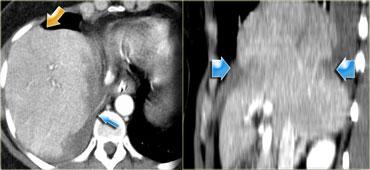

Bên trái là một biểu hiện phổ biến khác của chấn thương tụy.

Quan sát các hình ảnh và mô tả các phát hiện.

Sau đó tiếp tục.

Đây là tổn thương phối hợp theo vùng bên phải.

Có rách gan đi qua các mạch máu lớn kèm theo đứt ngang tụy tại vị trí nối giữa đầu và thân tụy.

Lực tác động phải đến từ phía trước bên phải, ép gan và tụy vào cột sống.

Đôi khi loại chấn thương này cũng liên quan đến tá tràng.